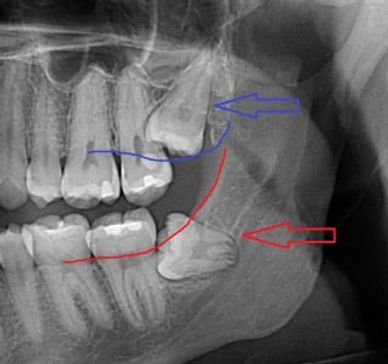

This means the teeth are underneath the tissue or within the bone and are not likely to fully come through.

We advocate removal of wisdom teeth after root formation start, which can range in age from 14-21. Our typical patient ages for this procedure are 15-26 years old. Common symptoms of impacted wisdom teeth that need to be removed include: